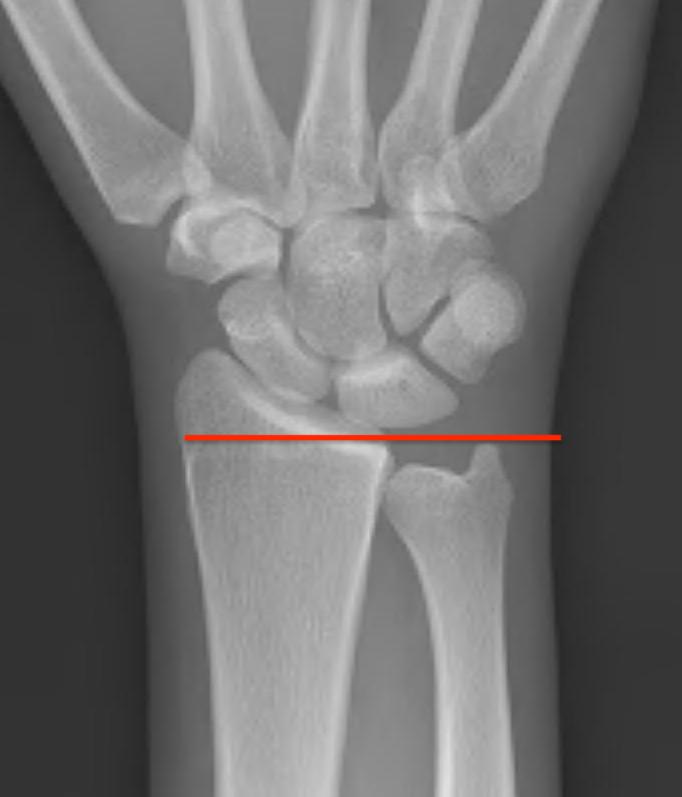

Ulna Variance

Supination and pronation alter variance

90 / 90 view (elbow 90° / shoulder abducted 90°)

- neutral supination / pronation

- PA film with wrist in neutral

- line from lunate fossa and ulna head

Ulna neutral

Ulna positive

Ulna negative